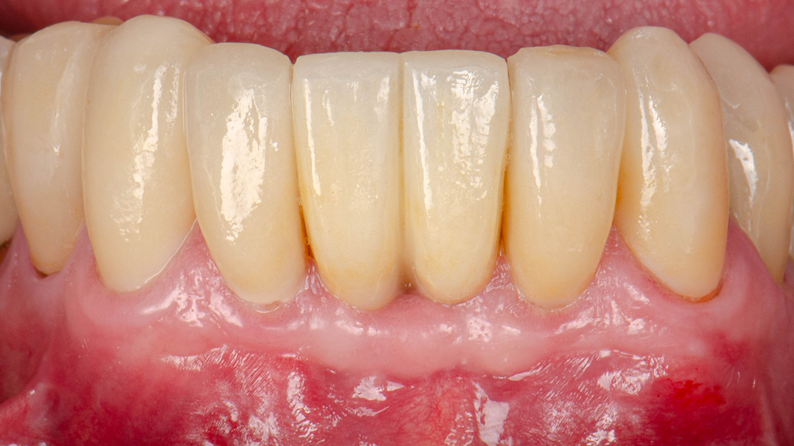

Paralelamente, os dentes naturais adjacentes (elementos 32, 33, 42 e 43) receberam laminados cerâmicos para harmonizar forma e cor com as novas coroas. Os laminados foram confeccionados em cerâmica vítrea de dissilicato de lítio (e.max), material renomado por sua estética e resistência. O dissilicato de lítio é uma cerâmica que combina excelentes propriedades mecânicas e estéticas, sendo um dos materiais mais utilizados para facetas e coroas devido a essa combinação de qualidades. Ele oferece variedade de cores e graus de translucidez que imitam com fidelidade a aparência do dente natural, além de apresentar resistência flexural na faixa de 360–400 Mpa – suficiente para uso seguro em dentes anteriores e posteriores unitários. Outra vantagem importante é sua capacidade de adesão ao dente remanescente, o que possibilita preparos minimamente invasivos e uma alta taxa de sucesso clínico a longo prazo. Com os laminados em dissilicato de lítio, obteve-se uma integração harmônica de cor e forma entre os dentes naturais restaurados e as novas coroas em implante, conferindo um sorriso estético e natural para a paciente.

Todo o processo foi conduzido visando excelência na adaptação e no selamento das interfaces protéticas. A utilização do fluxo digital, desde o escaneamento até a fresagem das peças, garantiu restaurações com margens precisas e ótimo assentamento nos preparos dentários e nos pilares dos implantes. Os laminados cerâmicos foram cimentados sob isolamento adequado, assegurando selamento marginal efetivo e proteção contra infiltrações. As coroas em zircônia sobre implante foram parafusadas aos pilares com torque controlado, garantindo estabilidade e vedamento na interface pilar-coroa. Ao final, ajustes oclusais mínimos foram necessários, dado que o planejamento virtual prévio já previu contatos balanceados.

Como resultado, a paciente recebeu uma reabilitação integrada de alta qualidade, unindo tecnologia digital e materiais cerâmicos avançados. As coroas implantossuportadas em zircônia monolítica proporcionam resistência e função, enquanto os laminados em dissilicato de lítio asseguram estética e biomimetismo. A adaptação precisa e o selamento adequado obtidos em todas as restaurações favorecem a longevidade do tratamento e a satisfação da paciente com seu novo sorriso.